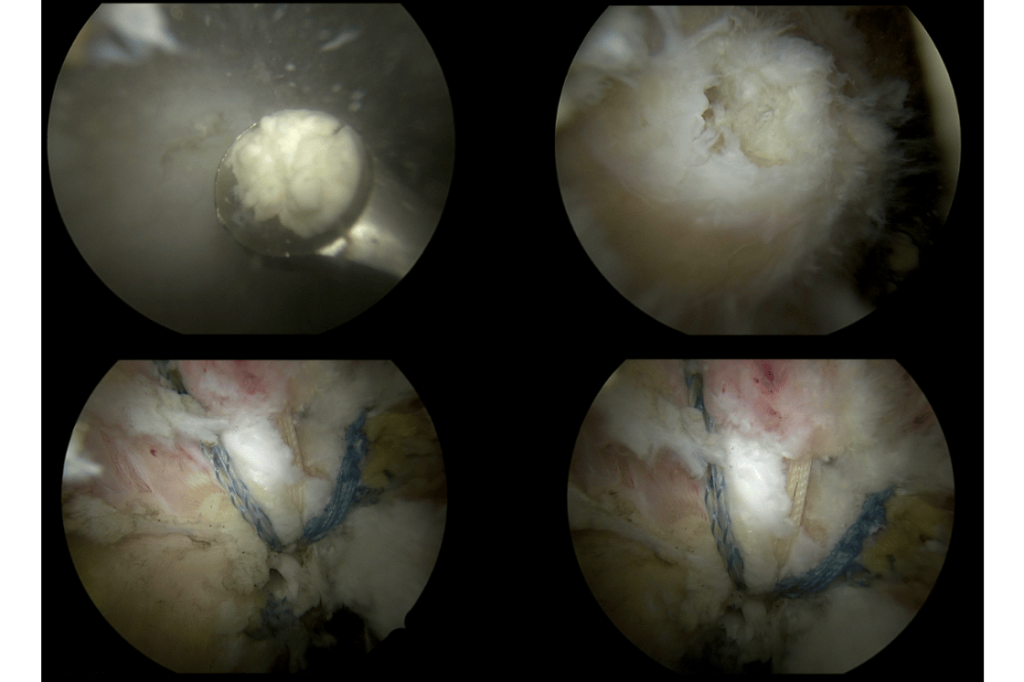

Kapalı cerrahi (artroskopik debridman) ile kalsiyum birikimi doğrudan görüntülenerek temizlenebilir. Ameliyat sırasında tendon içindeki kireç odakları özel aletlerle boşaltılır ve varsa çevre dokulardaki irritasyon giderilir. Gerekiyorsa tendon onarımı da aynı seansta yapılır. Bu yöntem, minimal doku hasarı ile maksimum fayda sağlar.

Artroskopik yöntem sayesinde iyileşme süreci açık cerrahiye göre daha hızlıdır, izler küçüktür ve hasta günlük yaşamına daha konforlu bir şekilde dönebilir. Başarı oranı yüksektir ve hastaların büyük çoğunluğu ağrısız, fonksiyonel bir omuza kavuşur.